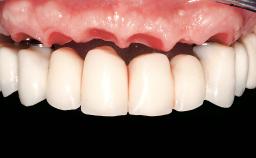

Immediate Loading of Six Implants in the Mandible and Six Implants in the Maxilla and Final Restoration with Full-Arch CAD/CAM Metal Framework FDPs Involving Digital Planning and Guided Surgery

Immediate loading of dental implants is increasingly popular with clinicians and patients. The idea of delivering a restoration directly after implant insertion,combined with a less invasive procedure (flapless protocol), has made treatment protocols involving dental implants more accessible to dentists and patients. However,immediate-loading concepts require sophisticated and exact planning. To facilitate this, conventional panoramic tomographs and periapical radiographs are often taken with the patient wearing a radiographic template simulating the preoperative prosthetic design. However, these radiographs do not provide all the necessary information. In addition, some protocols call for conventional surgical templates fabricated on the diagnostic cast. These will inform the bone drilling points and drill angles, but do not reference the underlying anatomical structures or provide exact 3-D guidance.